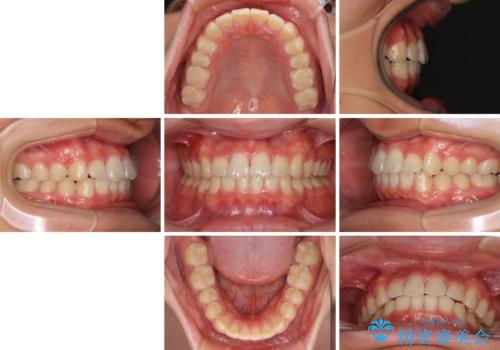

深い咬み合わせとデコボコ ワイヤー矯正で短期治療

- 前歯のデコボコを改善したいとのことで来院された患者様です。

インビザラインでの治療も可能でしたが、深い咬み合わせと奥歯の咬み合わせを改善するにあたり、ワイヤー矯正の方が治療期間を短縮できると判断し、ワイヤー矯正をお勧めしました。

結果として、1年かからずに奥歯の咬み合わせを改善することができました。